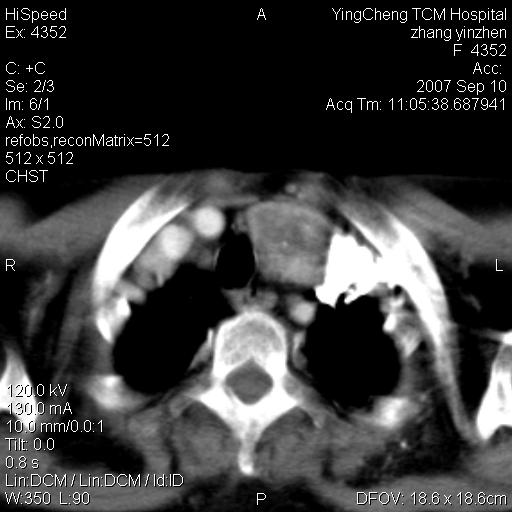

以下是引用卜一在2007-9-18 14:41:00的发言:[br]右肺肿块:毛刺+胸膜凹陷征+供血血管+浅分叶+强化。支持:周围性肺癌 !另:左侧甲状腺腺瘤!

以下是引用夏季在2007-9-18 11:00:00的发言:[br]1。右肺肿块,周围有短毛刺,肺门侧有血管与其相连,胸壁侧有胸膜凹陷征,考虑周围性肺癌 2。左侧甲状腺软组织肿块,内有高密度钙化灶,考虑左侧甲状腺腺瘤。